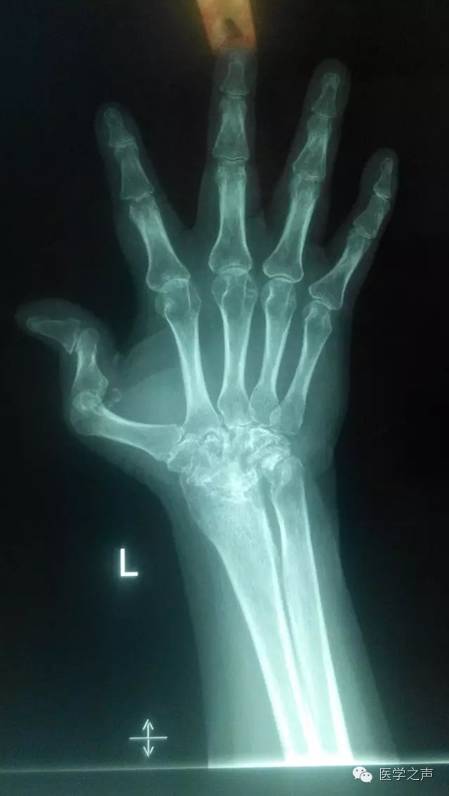

【病例】双手类风湿性关节炎1例X线影像表现

影像表现:

双手指间关节周围软组织稍肿胀,关节面模糊,关节间隙变窄,关节邻近骨质疏松,其间可见斑点状及小囊状骨质密度减低区,左手第1掌指关节及右手第5指关节呈半脱位,各腕骨骨质疏松,边缘不清,见斑点状及小囊状骨质密度减低区。

诊断意见:

1.双手类风湿性关节炎。

2.左手第1掌指关节及右手第5指关节呈半脱位。